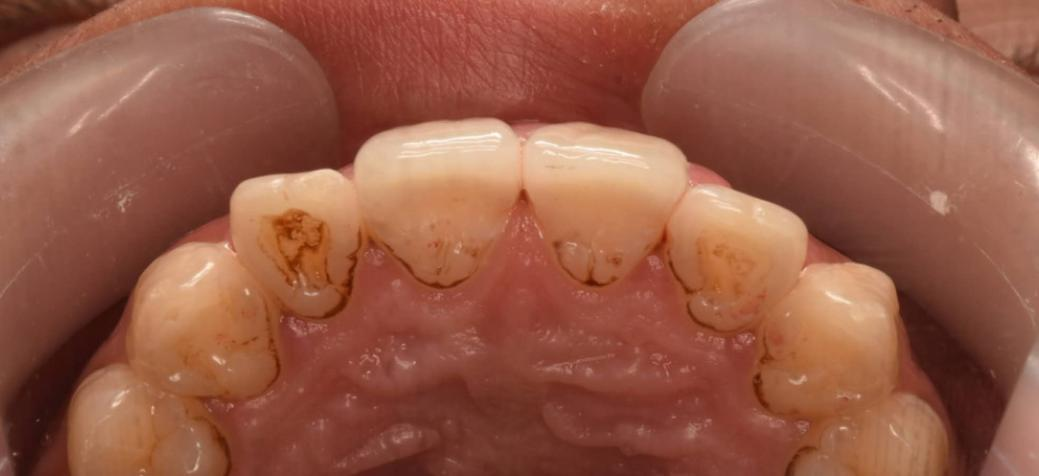

Many people don't know. In fact, when a tooth is broken, ultra-thin porcelain veneers or micro-veneers can be selected for restoration depending on the severity of the situation. As long as the pulp is not damaged, the broken surface can be slightly polished and then veneer restoration can be performed. Such as the teeth like the following:

The use of porcelain veneers to repair tooth defects is a very good method. It can be customized according to the specific conditions of the patient's teeth and fit the tooth surface perfectly. Porcelain veneers have excellent aesthetics, with realistic and natural colors, which can effectively improve the appearance of the teeth. At the same time, its material is strong and durable and can maintain a good repair effect for a long time.